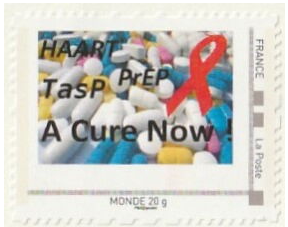

HAART PrEP TasP A cure Now - - - Agir pour la Paix - - - Association Raphael don d'organes